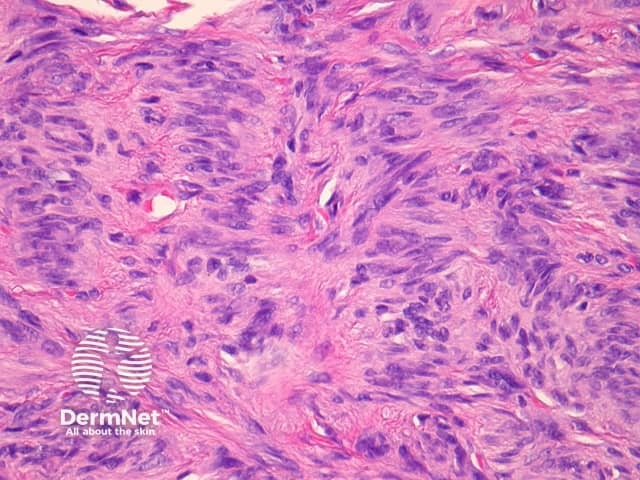

Sections through epithelioid dermatofibroma show a centrally located, circumscribed tumour underlying an epidermal collarette. The tumour is composed of cells arranged in sheets and sometimes a storiform pattern. Individual cells show epithelioid morphology with abundant eosinophilic cytoplasm with round vesicular nuclei and prominent nucleoli (figures 5, 6). The cells may be markedly enlarged and display some nuclear atypia and mitoses. There is frequently an associated inflammatory cell infiltrate which can be helpful for the diagnosis.

Figure 5

Figure 6